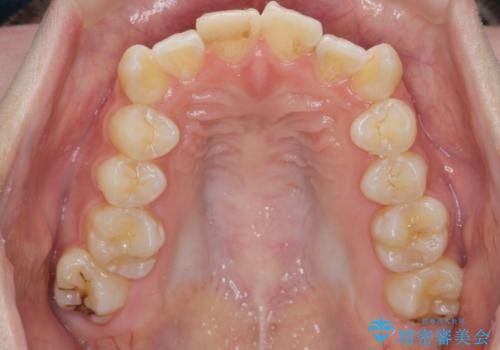

綺麗な歯並びを手に入れられたと同時に、口元もスッキリし、仕上がりに満足いただくことができました。

前歯の角度を改善するために小臼歯4本の抜歯を行いワイヤー マルチブラケットを用いて、しっかりと前歯の角度を改善する治療計画としました。